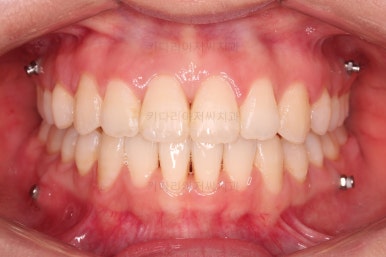

상하좌우 총 4개의 미니스크류를 이용해서 치열을 뒤로 당겨줍니다.

중간평가를 하면서 환자분과 가능한 수준/원하는 수준을 잘 조율해 가면서 입매를 정해갑니다.

종료 시 사진입니다.

중앙선, 교합, 치아배열 모습 모두 양호해졌습니다.